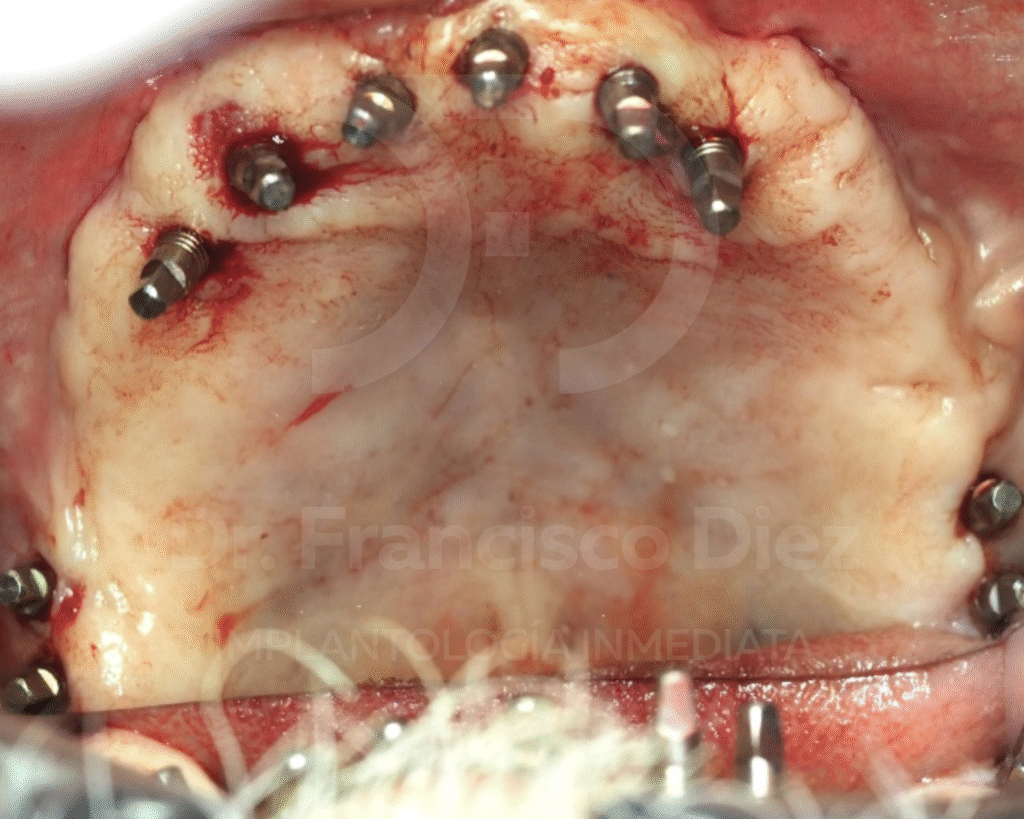

El día de la intervención se procede a todas las extracciones dentales y la explantación de los 4 implantes convencionales que llevaba. Inmediatamente después se colocaron 10 implantes córticobasales en la arcada superior (doble pterigoideo bilateral y 6 en piso nasal), y otros 8 implantes córticobasales en la arcada inferior (4 implantes en balcón lingual y 4 en sínfisis), y se realizó el escaneado de la boca para la realización de las prótesis.

Al día siguiente, se colocó ambas prótesis fijas de forma provisional, que se cambiarán a partir los 8 meses cuando se haya producido la regularización ósea y gingival, proceso normal que se produce tras las exodoncias, y que la prótesis definitiva tenga la mejor adaptación posible.